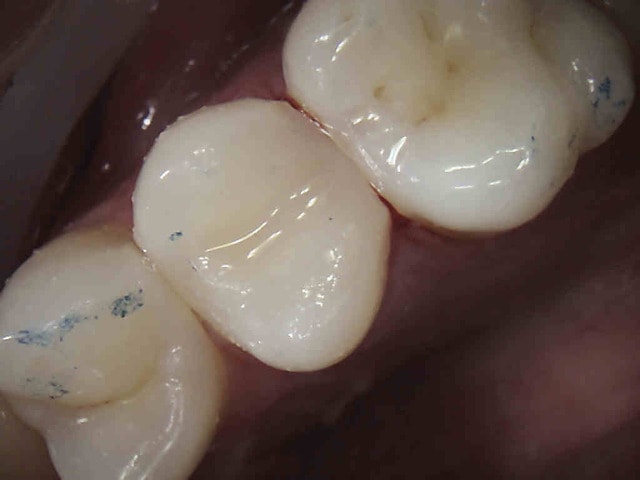

Tiens mon choupinet mutualiste.-))))

Au fait, t'as oublié la digue, pour ton compo. Une merde, quoi...

Pour la digue, sur les endos molaire seulement, il existe d'autres moyens moins chiants à poser pour les compos, il est en effet autrement plus chiant de poser la digue sur une demi arcade et surtout de façon compatible avec les matrices ( le v3 ring n'aime pas les clamps à ailettes). Mais tu devrais le savoir non ?

J'y travaille pour trouver un moyen simple et efficace pour poser la digue dans toutes les situations comme celle ci dessous. Tiens c'est tout frais, endo sc33 en 1 temps, 1H 15 et encore je n'ai pas d'assistante au fauteuil.